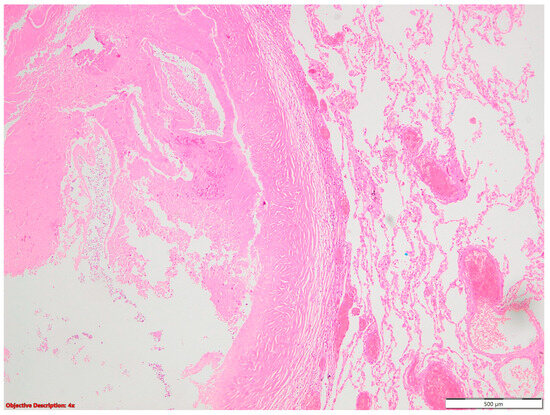

A histopathological examination of surgical resection specimens highlighted the presence of the following associations between NSCLC and other tumoral and nontumoral, and infectious and noninfectious pathological lesions, including nine cases of granulomatous inflammation, ten cases of fibronodular lesions, five cases of fibronecrotic nodules (Figure 1), two nodular calcifications, four instances of osseous/osteomedullary metaplasia, three cases of pneumoconiosis, two benign tumors, four lung infarctions, one instance of aspiration pneumonia, and one meningothelial-like nodule (Table 1).

Figure 1. Fibronecrotic nodule (left side) in the lung parenchyma (right side); HE, 40×.